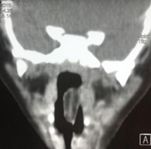

Figure 1 Computed tomography revealed a tumor of 2.5 cm by 0.5 cm pedicled to the left lateral wall of the cavum that fell towards the supraglottis.

Figure 2 No other alterations were found.